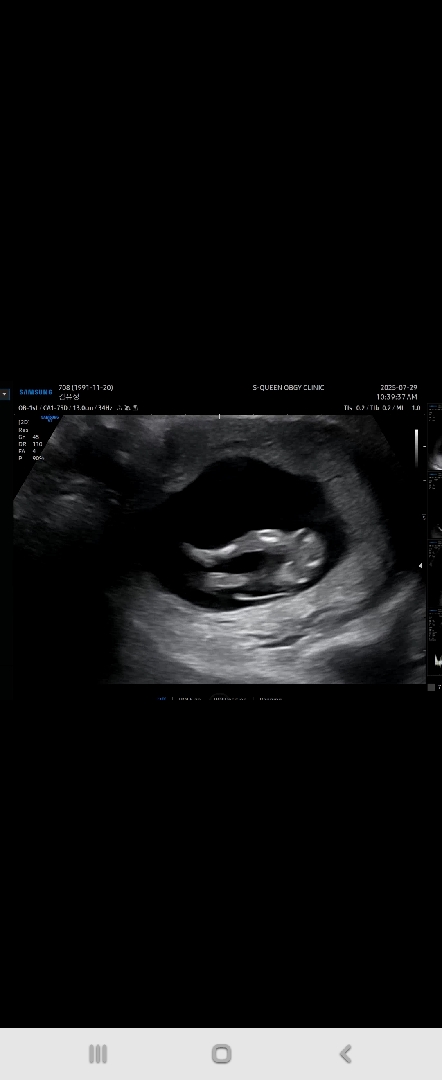

성별..딸맞겠죠 ㅋ

12주차 사진이에요ㅎㅎ